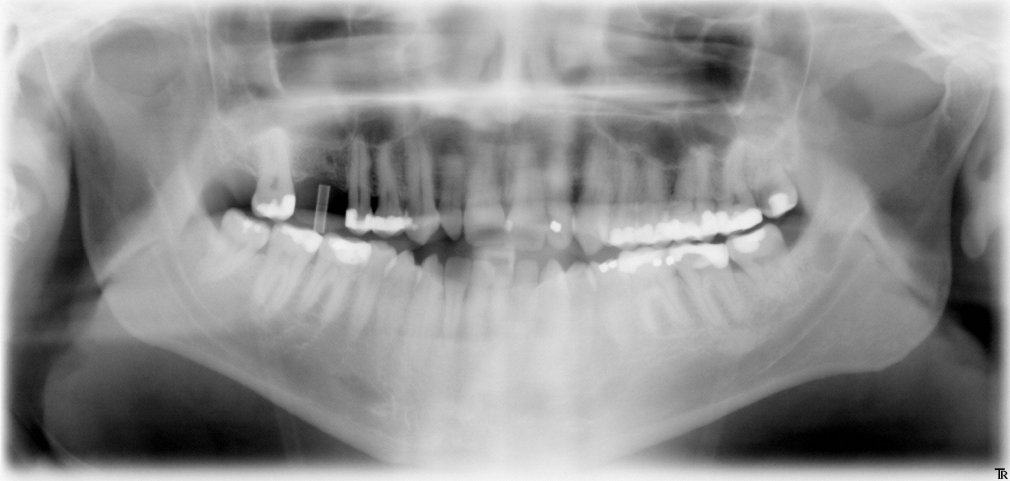

Panorama-Röntgenaufnahme

Für ein Implantat werden sowohl eine Mindest-Knochentiefe als auch ein Sicherheitsabstand im Unterkiefer zum Nervenkanal vorausgesetzt. Die Knochentiefe wird durch spezielle Röntgendiagnostik ermittelt.

Die reale Knochenhöhe wird mit Hilfe einer Tiefziehschiene mit eingearbeiteten Metallkugeln ermittelt. Bei digitalen Röntgengeräten kann gegebenenfalls auf die Messaufnahmen verzichtet werden, da sie über ein integriertes Messtool verfügen. Zur Detailabklärung kann es erforderlich sein, zusätzliche Aufnahmen von einzelnen Zahnabschnitten zu machen.